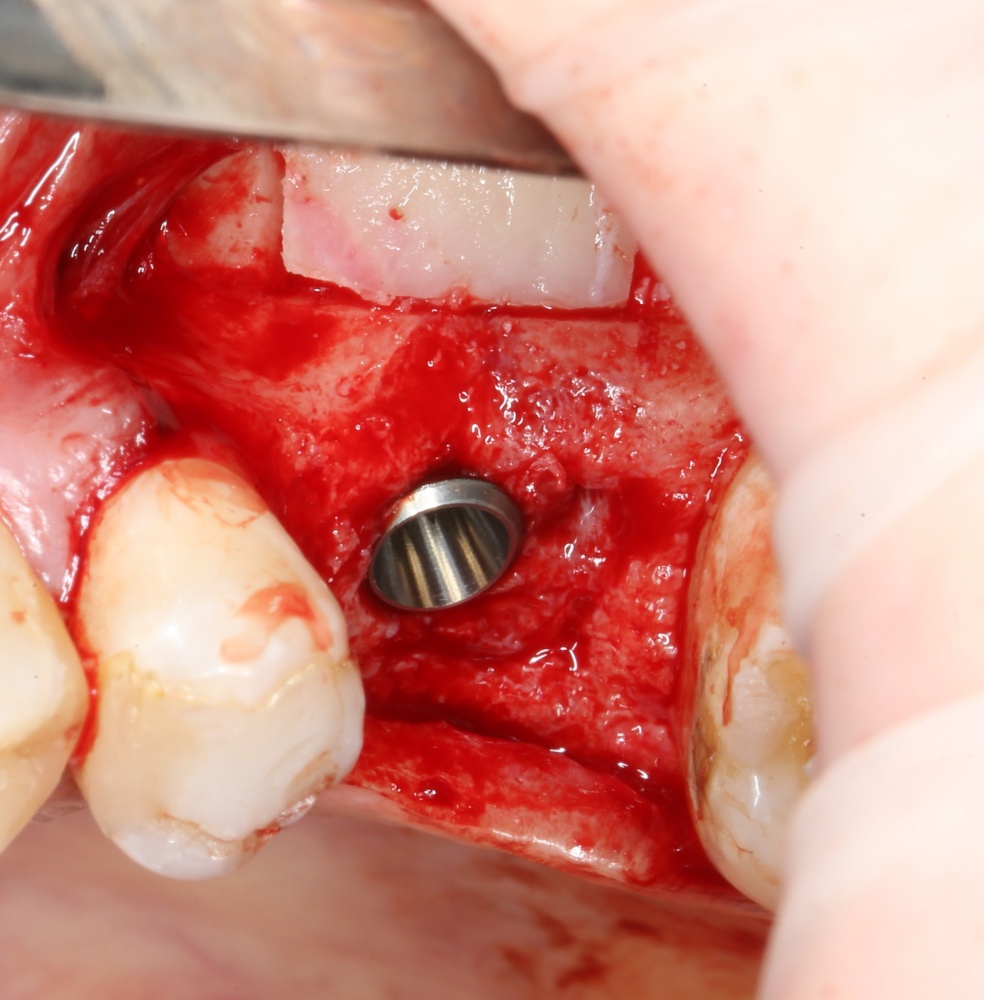

Кортикальная фреза погружается строго до отметки (см выше). В нашем клиническом случае (с синуслифтингом) это особенно важно, чтобы имплантат не улетел в субантральное пространство. Таким образом получаем лунку, полностью конгруэнтную будущему имплантату. Это очень-очень важно:

Если лунка подготовлена правильно, то имплантат проваливается в неё почти полностью: